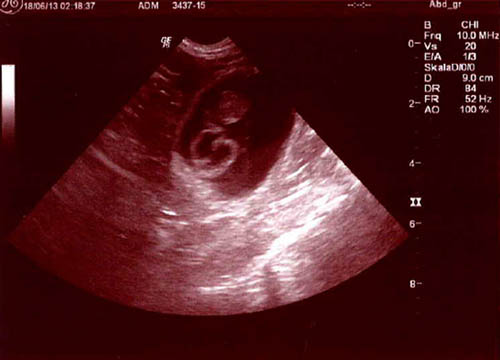

Heute waren wir zur Ultraschalluntersuchung und haben nun Gewissheit, dass Samba tragend ist. Havaneserwelpen sind unterwegs. Wir freuen uns riesig!

In diesem Trächtigkeitsstadium kann zwar eine Trächtigkeit Diagnostiziert werden, aber die genaue Welpenanzahl ist immer eine Überraschung.

Havaneserwelpe circa 2 Zentimeter gross